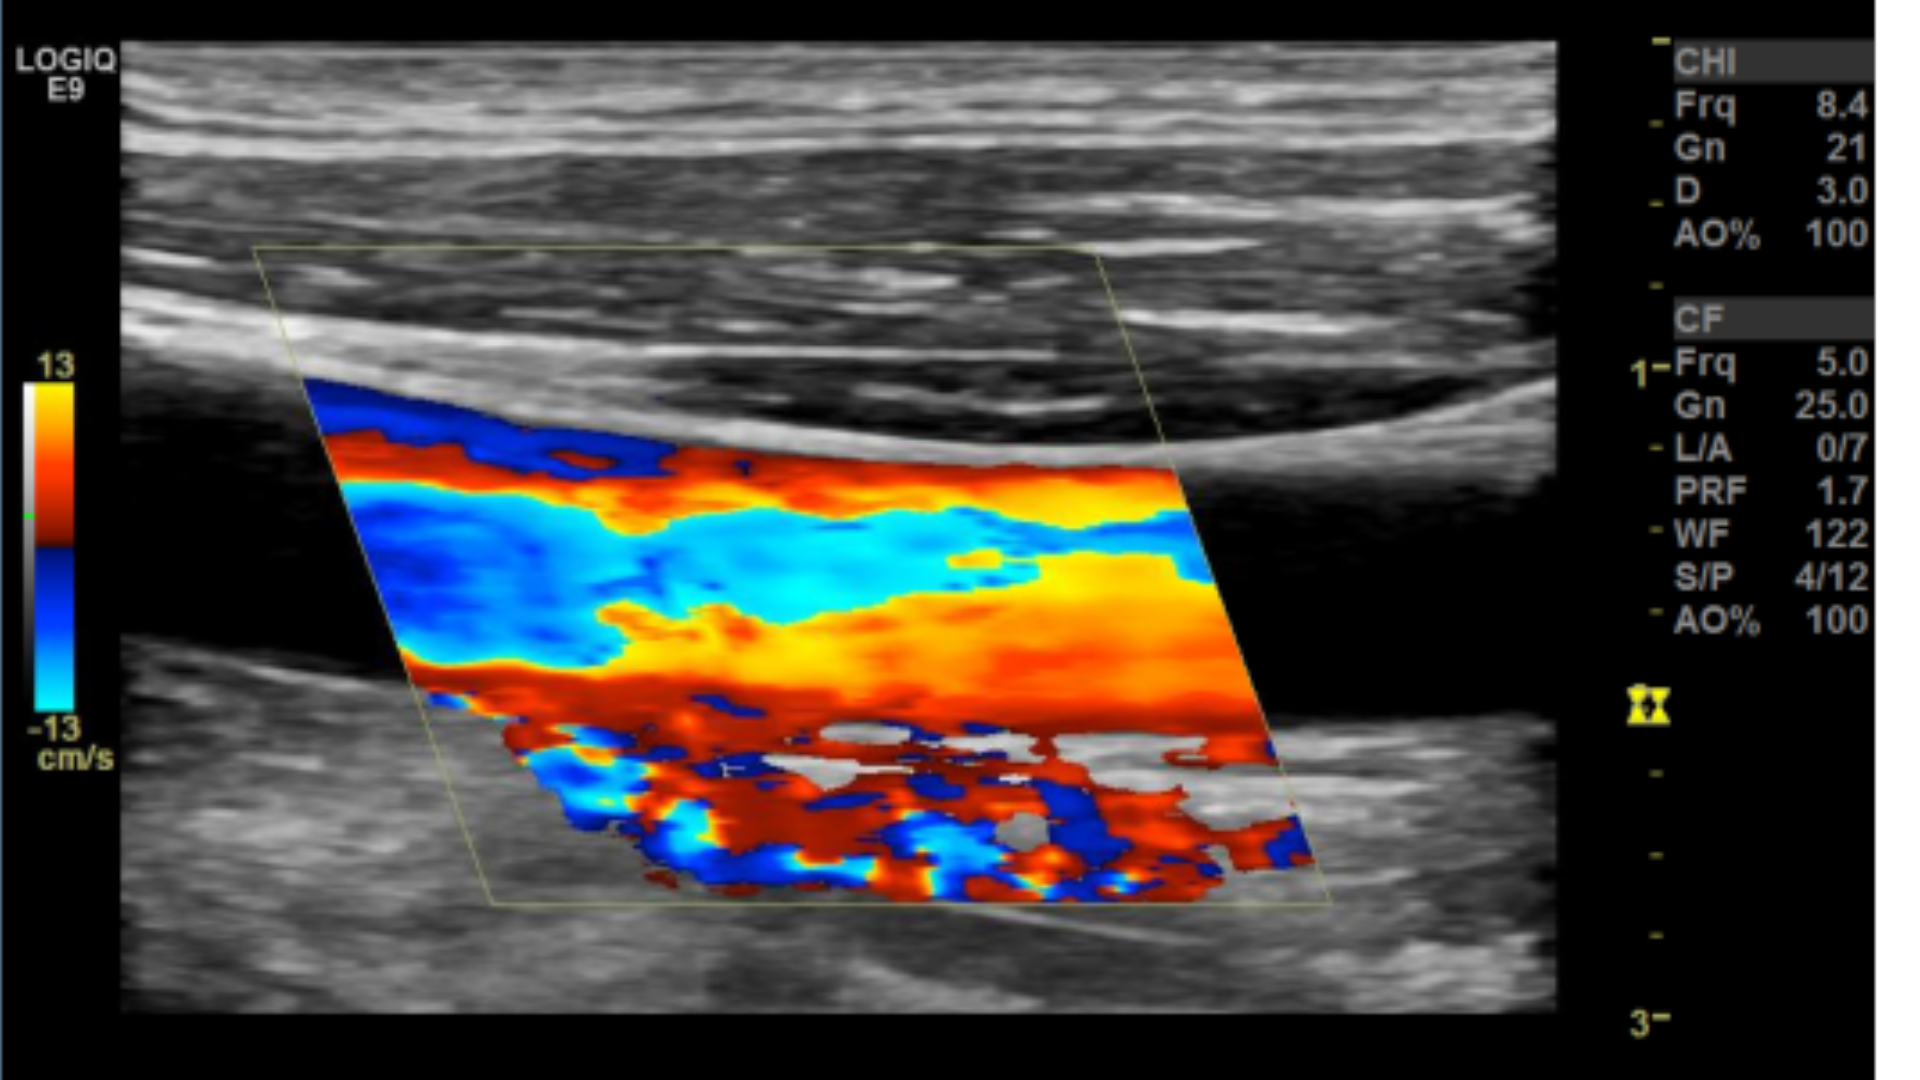

Many people have trouble on how to set the color box. A quick way to get it right is to make sure the steered ultrasound beam and vessel meet an acute angle 60° or less.

Correct Color box angle

Sub-optimal angle

Incorrect angle